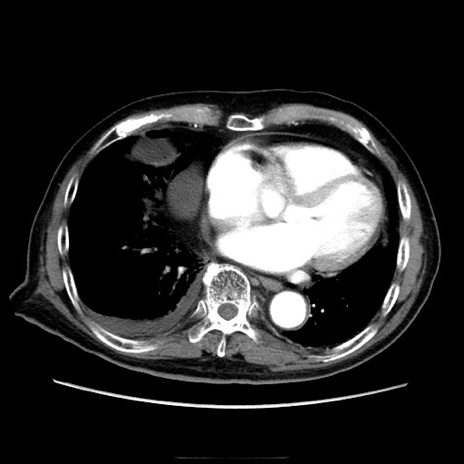

冠状断像

【症例】70歳代男性

【主訴】腹痛

【現病歴】肝硬変・肝細胞癌にてかかりつけの方。約9時間前に食後より腹痛出現。症状が徐々に増悪し、嘔吐出現したため来院。

【既往歴】肝硬変、肝細胞癌(RFA、TACE後)

【身体所見】意識清明、表情苦悶様、BT 36℃、BP 129/78mmHg、P 88bpm、SpO2 97%(RA)、右上腹部から心窩部にかけて圧痛あり、反跳痛なし、筋性防御あり。

【データ】WBC 5800、CRP 0.16